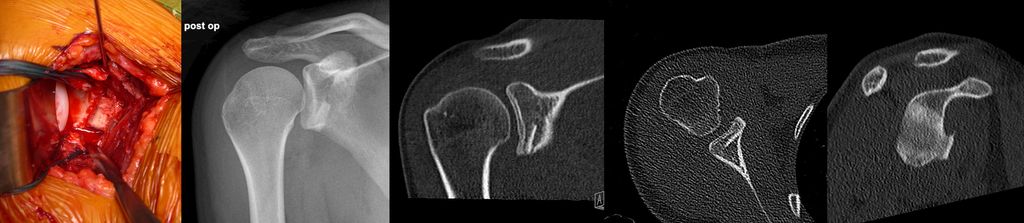

Das Risiko des Vorhandenseins von Knochendefekten am Glenoidrand wird allgemein unterschätzt, daher ist eine Computertomografie (CT) bei Rezidivinstabilitäten obligat. Insbesondere bei chronischen glenohumeralen Instabilitäten nach Voroperation sind knöcherne Läsionen nahezu immer vorhanden und es gilt, deren Größe und Lokalisation zu erfassen. Neben Standardschichtungen sollte eine 3D-Rekonstruktion des Glenoids unter Subtraktion des Humerus („en face view“) durchgeführt werden, um Pfannenranddefekte zu quantifizieren.39–41 Für die Erfassung der Größe eines Knochendefektes am Glenoid stehen verschiedene Methoden zur Verfügung.42 In den meisten Fällen wird in der „en face view“ ein „best fit circle“ zur Quantifizierung des Knochendefektes herangezogen43 (Abb. 1). Das Zentrum dieses Kreises liegt grob im Bereich des „bare spot“. Bei der Pico-Methode wird durch Überlagerung mit der gesunden Seite die Fläche des Defektes errechnet.44 Andere errechnen das Ausmaß des Defektes unter Verwendung der Distanzen zum „bare spot“.45 Außerdem wird anhand der CT auch ermittelt, ob es sich um eine monopolare oder bipolare Läsion handelt, also auch am Humeruskopf eine relevante Läsion vorliegt, und ob eine „on-track“ oder „off-track“ Läsion vorliegt46 (Abb. 2).

Abb. 1: In den meisten Fällen wird bei der CT-Bildgebung in der „en face view“ ein „best fit circle“ zur Quantifizierung des Knochendefektes herangezogen

Abb. 2: Anhand der CT wird auch ermittelt, ob es sich um eine monopolare oder bipolare Läsion handelt, also auch am Humeruskopf eine relevante Läsion vorliegt, und ob eine „on-track“ oder „off-track“ Läsion vorliegt